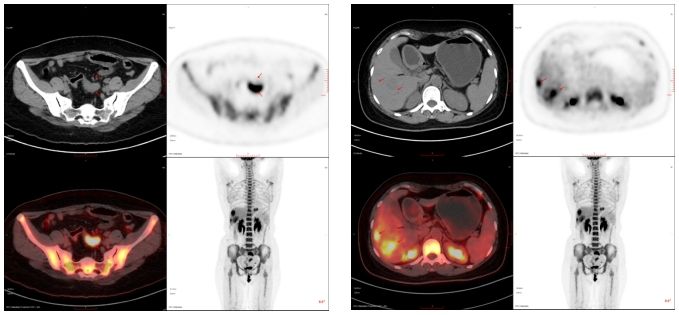

66岁,女,左侧腰骶部疼痛1月,ECT检查示:胸7、骶1及左侧髂骨多发骨代谢异常,考虑肿瘤性病变,转移瘤?

PET/CT诊断:右肺上叶后段结节,代谢增高,考虑原发恶性病变(右肺上叶后段周围型肺Ca)伴、肺内、淋巴结及多发骨转移。